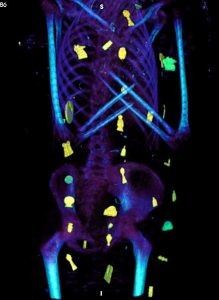

كما أوضحت صور الأشعات المقطعية الثنائية والثلاثية الأبعاد عن وجود حوالي 49 تميمة مرتبة ترتيبًا منمقًا في ثلاث أعمدة بين طيات اللفائف الكتانية وبداخل تجويف المومياء. كما أظهرت الأشعة أيضا 21 شكلًا مختلفًا للتمائم مثل عين المعبود حورس والجعران وتميمة الأفق والمشيمة وعقدة إيزيس والريشتان، وغيرهم.

ومن خلال نتائج قياسات الأشعة تبين أن 30 تميمة من التمائم المكتشفة داخل المومياء صنعت من الذهب بينما باقي التمائم صنعت من الأحجار أو الفيانس، بالإضافة إلى تميمة علي شكل لسان من الذهب وضعت بداخل فم المتوفي ليتمكن من التكلم في العالم الآخر، كما يوجد تميمة على شكل أصبعين أسفل الجذع لحماية فتحة التحنيط، وتميمة أخرى كبيرة من الذهب لجعران القلب موجودة بداخل تجويف صدر المومياء، والذي تم عمل مستنسخ منه باستخدام الطباعة ثلاثية الأبعاد.

وأكدت الدكتورة سحر سليم أن الدراسة كشفت عن وجه المومياء لأول مرة بعد إزالة اللفائف بشكل افتراضي بتقنية الأشعة المقطعية، حيث أتاحت الدراسة فرصة فريدة لاكتشاف أسرار تحنيط المومياء دون المساس باللفائف، وكما تركها المصريين القدماء.